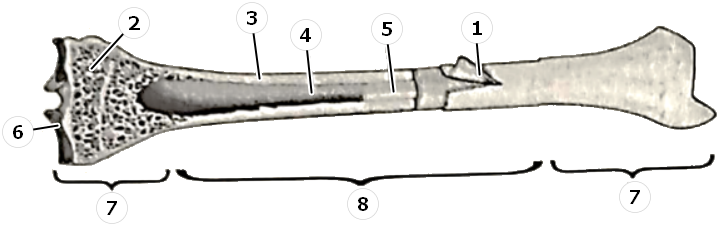

Изучение костного мозга: анатомия и функции